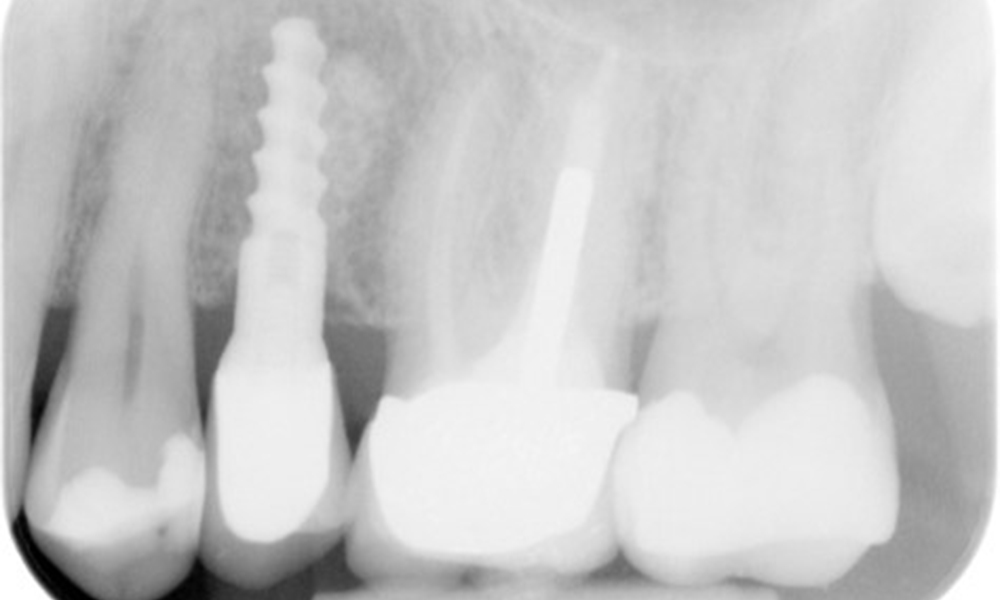

The X-ray image shows the bone loss

The X-ray images show the bone loss.

OPG: 29/02/2024

X-ray images (or bitewing X-rays)

X-ray images (or bitewing X-rays) taken on: 18/02/2021